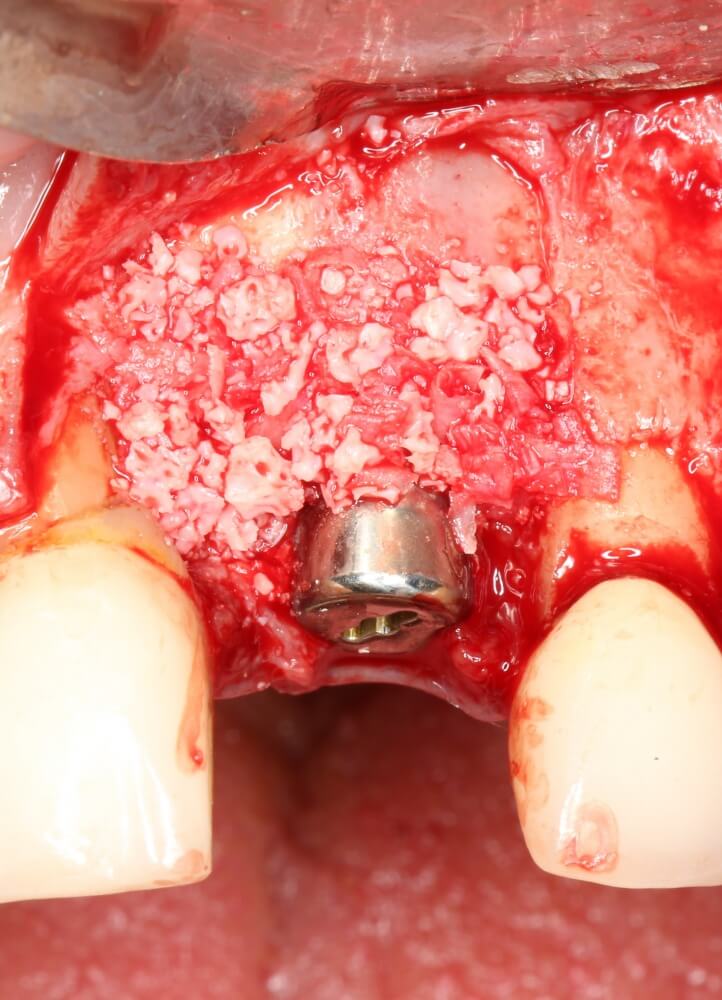

Рекомендации по установке имплантов. Для всех. Часть V.